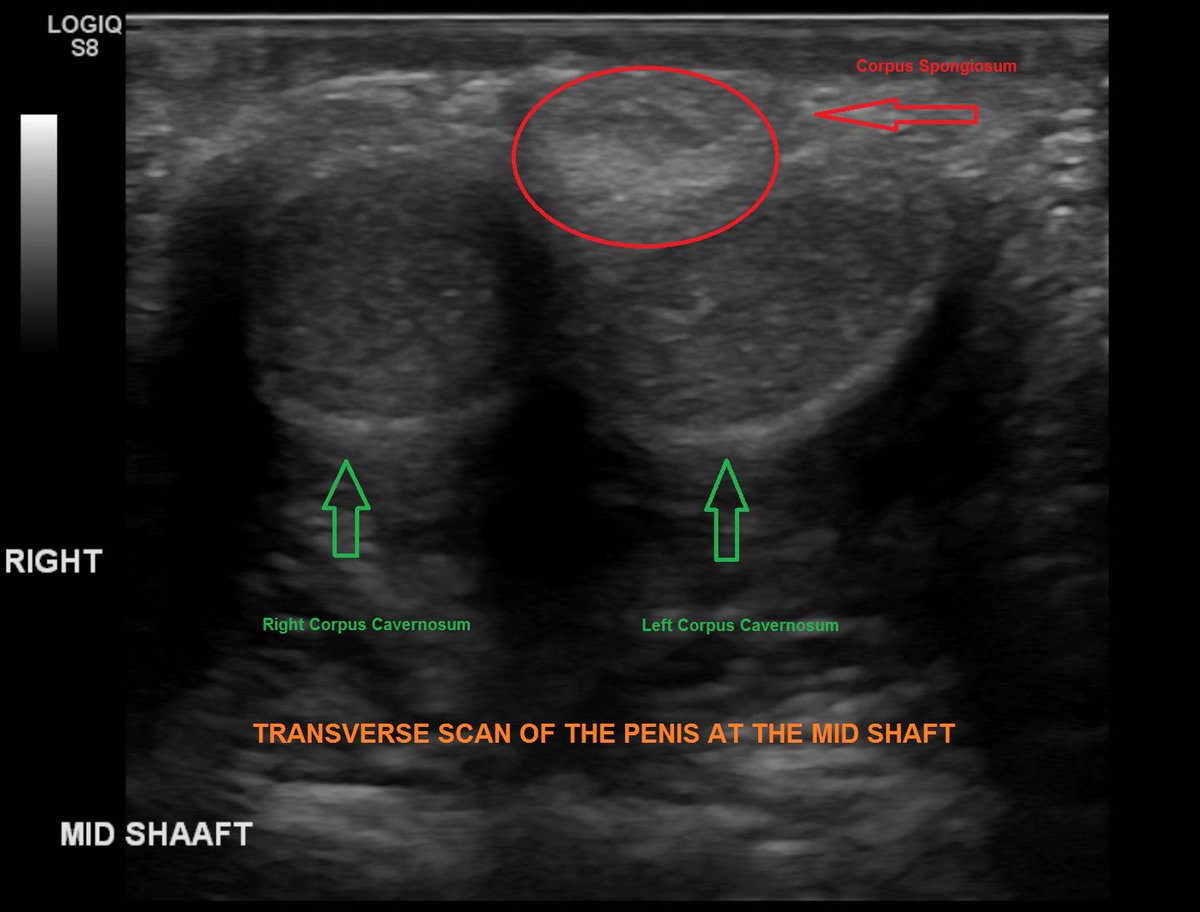

Irrespective of the indication for penile ultrasound routine scanning during penile ultrasound should include both transverse and longitudinal views of the penis by placing the transducer probe on the dorsal or ventral aspect of the penis. Treatment consists of noninvasive low-intensity sound waves that pass through erectile tissue restoring natural erectile function by clearing plaque out of blood vessels and encouraging the growth. Erectile dysfunction cannot be diagnosed solely on the basis of a penile ultrasound examination.

Pharmaco Penile Duplex Ultrasonography in the Evaluation of Erectile Dysfunction J Clin Diagn Res. Penile Duplex Ultrasound for Detecting Vascular ED Penile abnormalities ie some plaques of Peyronies disease fractures of the corpora cavernosa thickening of the tunica albuginea and septum may be easily displayed by B-mode investigation in the flaccid state. Erectile dysfunction is a common condition.